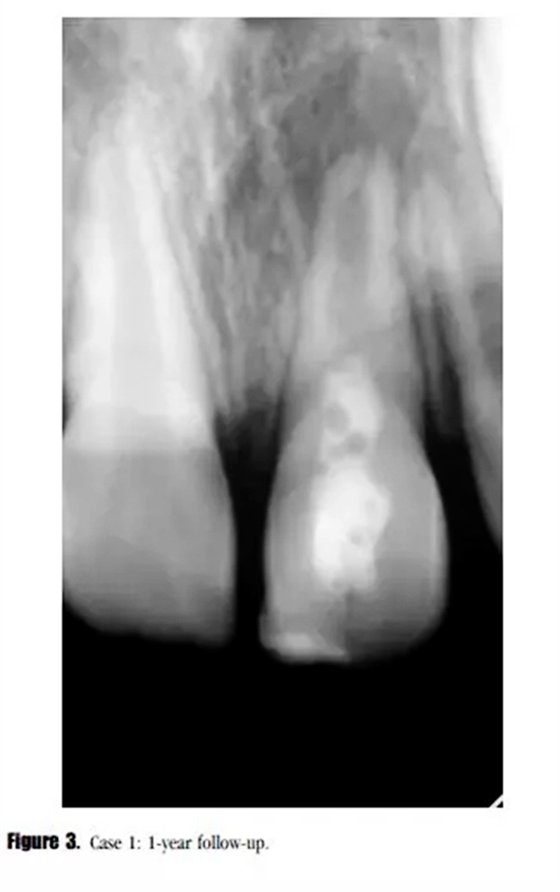

在第12個月的評估中,叩診與捫診又輕微不適。在臨床牙冠上未發(fā)現(xiàn)充填材料與牙體的縫隙以及隱裂線,探診深度正常。我們采用了一種細菌加強型封閉劑來預(yù)防再感染。影像學評估顯示,根尖周投射影增大、牙根停止發(fā)育,以及近中根管內(nèi)壁的輕微吸收。(圖3)

診斷為治療后的牙髓疾病復(fù)發(fā)。與患者家長商談,1個月后進行常規(guī)根管治療。根管內(nèi)使用 Total Fill RRM ( FKG Dentaire SA , La Chaux-de-Fonds , Switzeland )進行單尖充填(圖4)。